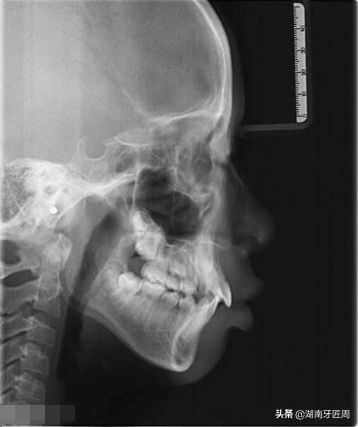

头颅侧位片

牙片主要有全景片(大片)和根尖片(小片)和头颅侧位片,必要时可做口腔科电子计算机X线体层摄影(CBCT)辅助检查。

牙齿在牙片上显示出白色阻射影像,牙釉质阻射最强,牙本质和牙骨质阻射低于牙釉质,牙髓腔呈黑色透明影像,根管口至根尖孔呈逐渐变细的影像。